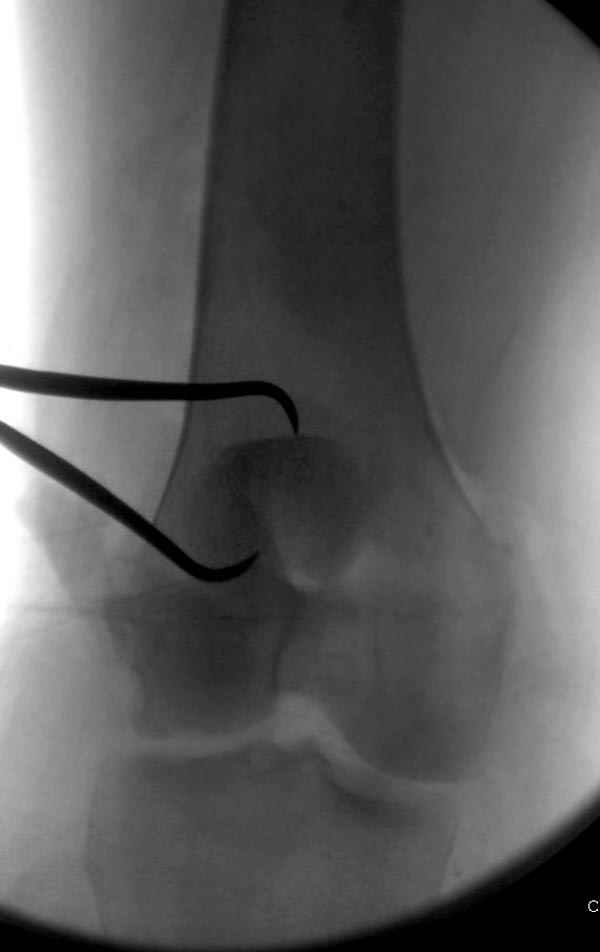

Сегодня досылаю остальные снимки, которые не прошли вчера. Как вчера писал, после фиксации перелома надколенника с дефектом кости и собственной связки, наложили ваккуум и наружный фиксатор. (снимки 4-9)

Внешний фиксатор держим около 6 недель, поэтому был выбран метод фиксации шурупами и еще линия перелома была диагональной, не было нужды в tension band technique, cannulated screws удобнее, провел спицы и по ним шурупы.

Связка ушита обычными сухожильными швами конец в конец, не было нужды проведения шва через надколенник, из-за ех-фиксатора.